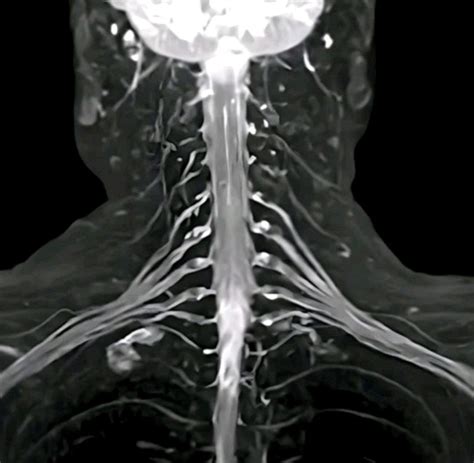

When chronic pain, numbness, or weakness persists without a clear explanation from standard diagnostic imaging, physicians may turn to more specialized techniques to pinpoint the source of the problem. One such advanced diagnostic tool is MRI Neurography. Unlike conventional MRI scans, which are primarily designed to visualize bones, muscles, and soft tissues, this specialized imaging technique is specifically engineered to provide detailed, high-resolution views of the peripheral nerves throughout the body. By enhancing the visualization of nerve fibers, MRI Neurography allows clinicians to detect subtle abnormalities, compressions, or lesions that might otherwise go unnoticed, playing a critical role in the accurate diagnosis and management of complex neurological conditions.

At its core, MRI Neurography is a sophisticated imaging protocol that utilizes powerful magnetic fields and radiofrequency pulses to create detailed maps of the peripheral nervous system. While traditional MRI sequences are effective for identifying large structural issues, they often lack the contrast necessary to differentiate nerve tissue from surrounding structures like fat, connective tissue, or blood vessels.

To overcome this, this specialized imaging employs specific pulse sequences designed to suppress the signal from fat—which often obscures nerve detail—while enhancing the signal from water-rich tissues like nerves. This process effectively makes the nerves "light up" on the resulting images, allowing radiologists to assess their anatomy, signal intensity, and trajectory in high detail.

• Brachial Plexus Injuries: Evaluating trauma or inflammatory conditions affecting the network of nerves that control the shoulder, arm, and hand.